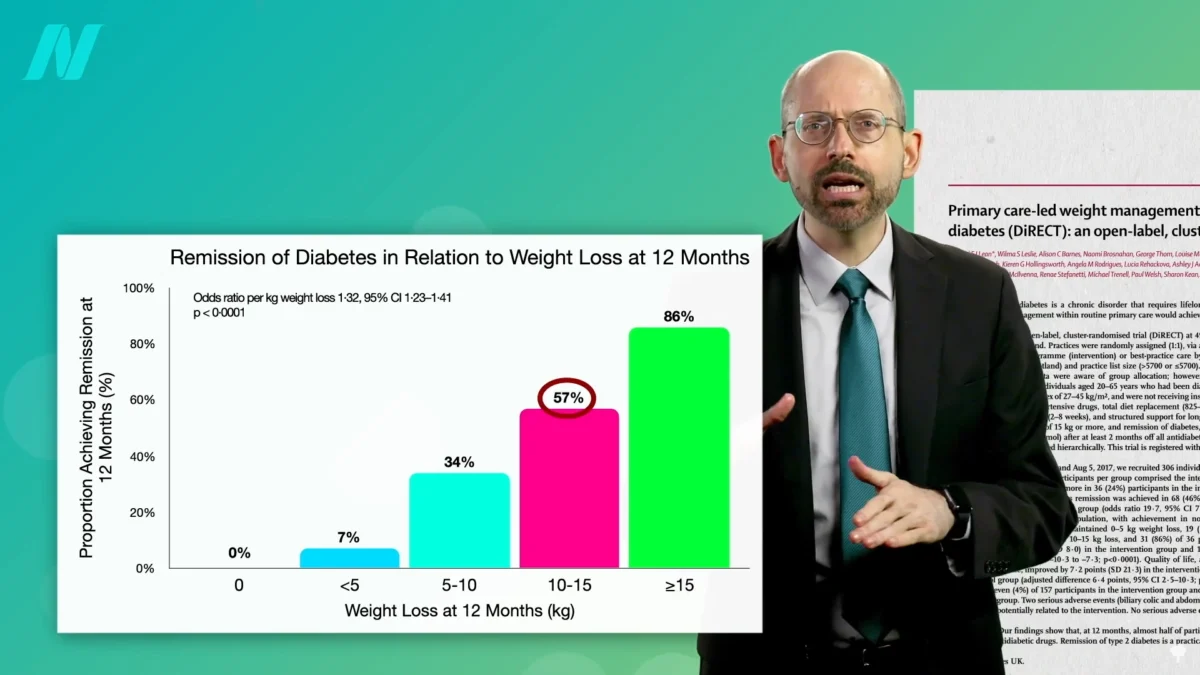

Promising Short-Term Effects Observed in Recent Studies, But Long-Term Efficacy Remains an Open Question

A comprehensive analysis of recent scientific studies has illuminated a series of encouraging short-term outcomes associated with a particular area of research, though significant questions persist regarding its long-term efficacy…